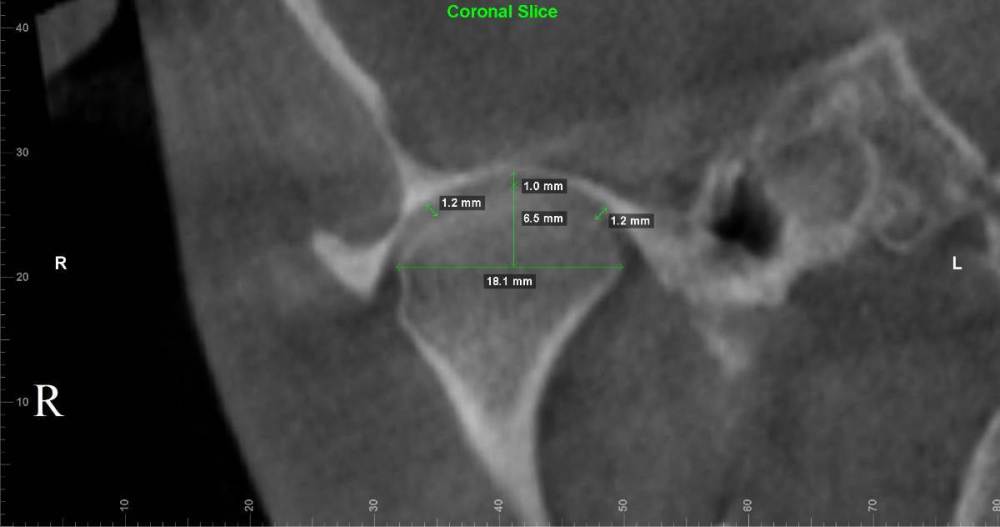

Lotos123 Опубликовано 24 ноября, 2022 Поделиться Опубликовано 24 ноября, 2022 чувствую боль справа и щелчки слева Ссылка на комментарий